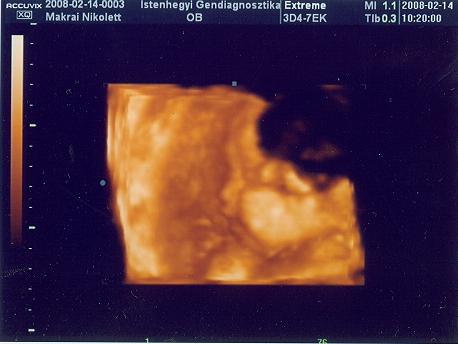

31 hetes